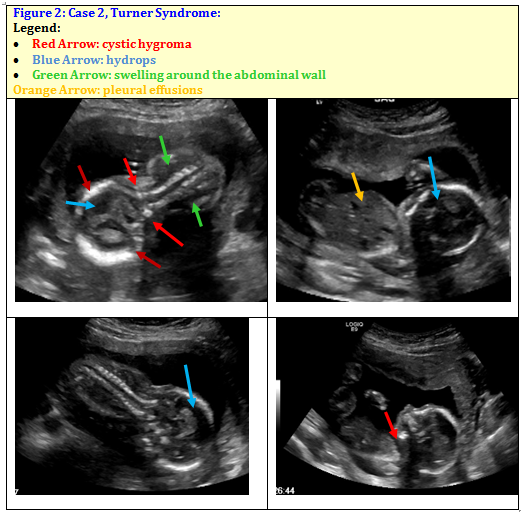

A 42 year old Caucasian female, Rh negative/antibody negative, G5P3013, at 15 weeks and 3 days gestation by last menstrual period (LMP) presented to clinic for her first obstetric ultrasound. Bedside ultrasound showed a live intrauterine pregnancy and corrected gestational age of 16 weeks 0 days. Ultrasound also revealed presence of swelling around the abdominal wall and fetal head (Figure 2).

Figure 2 Case 2, Turner Syndrome: Ultrasound revealed intrauterine fetal demise (IUFD), Massive cystic hygroma, significant hydrops with bilateral pleural effusions and ascites seen as presence of swelling around the abdominal wall and swelling around fetal head, Probable female fetus.

The patient was referred to the maternal fetal medicine service (MFM) for further evaluation of suspected fetal fluid collection as noted above. The MFM ultrasound at 17 weeks 3 days gestation revealed intrauterine fetal demise (IUFD), massive cystic hygroma and significant hydrops fetalis with bilateral pleural effusions and ascites consistent with hydrops fetalis. The ultrasound suggested a female fetus. As the antibody screen was negative, suggesting nonimmune hydrops, most likely due to fetal Turner syndrome (45XO). Patient declined noninvasive prenatal testing (NIPT) or amniocentesis to confirm diagnosis. She also declined dilatation/evacuation for termination and opted for induction of labor due to fetal demise. The patient was induced with 400 mcg of Misoprostol vaginally every 6 hours until delivery of a stillbirth female fetus. The remainder of her hospital course was uncomplicated.

Similarly, Turner syndrome can be detected on ultrasound but initial findings are less specific than with Pentalogy of Cantrell. Ultrasound findings associated with Turner syndrome are cystic hygroma and fetal hydrops in a female fetus.9,14,15 A cystic hygroma is an enlargement of lymphatic ducts and accumulation of lymph causing increased nuchal translucency.9,16 Fetal hydrops is defined as greater than 2 of the following; ascites, pleural effusions, pericardial effusion, or generalized and skin edema.16 Nuchal thickness is a common initial finding, as in this case, and may be accompanied by hydrops fetalis leading to fetal demise. Findings in this case included a massive cystic hygroma (Figure 2 red arrow), significant hydrops (Figure 2 blue arrow) with bilateral pleural effusions (Figure 2 orange arrow) and ascites. Although diagnosis was not confirmed with post-mortem genetic testing (per patient request) these findings, along with spontaneous fetal demise, are highly suggestive of Turner syndrome.14